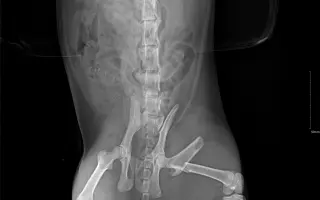

Fotogalerie